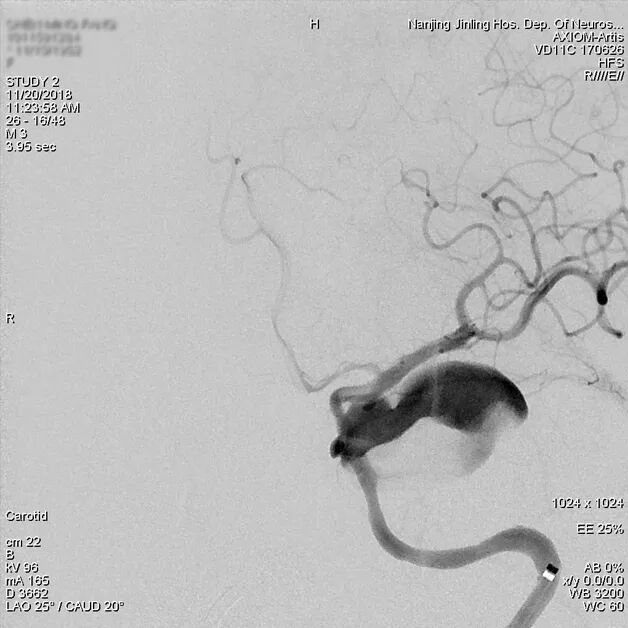

最后造影显示载瘤动脉通畅,瘤内血流有滞留。3D重建示支架贴壁良好。

为什么要用到微导管张鑫教授:“球囊锚定微导管辅助到位”技术在Pipeline Flex治疗复杂动脉瘤手术中的应用_https://www.jmylbn.com_新闻资讯_第12张

支架释放后造影,瘤内血流明显减缓,造影剂滞留

为什么要用到微导管张鑫教授:“球囊锚定微导管辅助到位”技术在Pipeline Flex治疗复杂动脉瘤手术中的应用_https://www.jmylbn.com_新闻资讯_第13张

为什么要用到微导管张鑫教授:“球囊锚定微导管辅助到位”技术在Pipeline Flex治疗复杂动脉瘤手术中的应用_https://www.jmylbn.com_新闻资讯_第14张

3D重建示支架全程贴壁良好